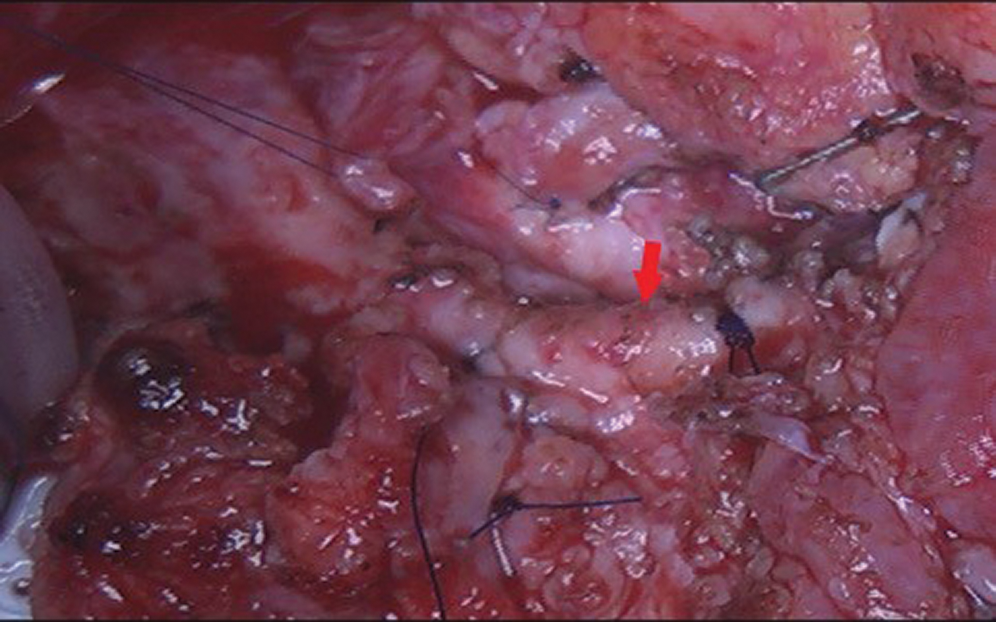

After redo-sternotomy, normothermic cardiopulmonary bypass (CPB) was instituted by central canulation and bicaval venous drainage. Careful dissection of the ascending aorta and complete isolation of the overriding common pulmonary artery with its right and left branches was made with the beating heart. After vena cava exclusion, a transverse incision was made on the main pulmonary artery and the retroperfusing “LAD” was identified (sinus 1) with his proximal stenotic segment and multiple collateral epicardial vessels (Fig. 5). Excision of this accessory LAD with a small pulmonary wall flange was made and an additional mobilization of the vessel over 2 cm was performed. Excision of the proximal stenotic segment was made with a small posterior split and calibration of the vessel till 2 mm diameter. Direct closure of the harvest site on the CPA was made. The appropriate coronary reimplantation site on the left anterolateral side of the aorta was identified after adequate aortic root and heart filling. Excision of a 3 mm aortic wall flange was performed after aortic clamping and bulbar cardioplegia. The “LAD” was reimplanted with 8/0 polypropylene continuous suture (Fig. 6).

Figure 5: Intraoperative views: Stenotic proximal segment of the accessory LAD